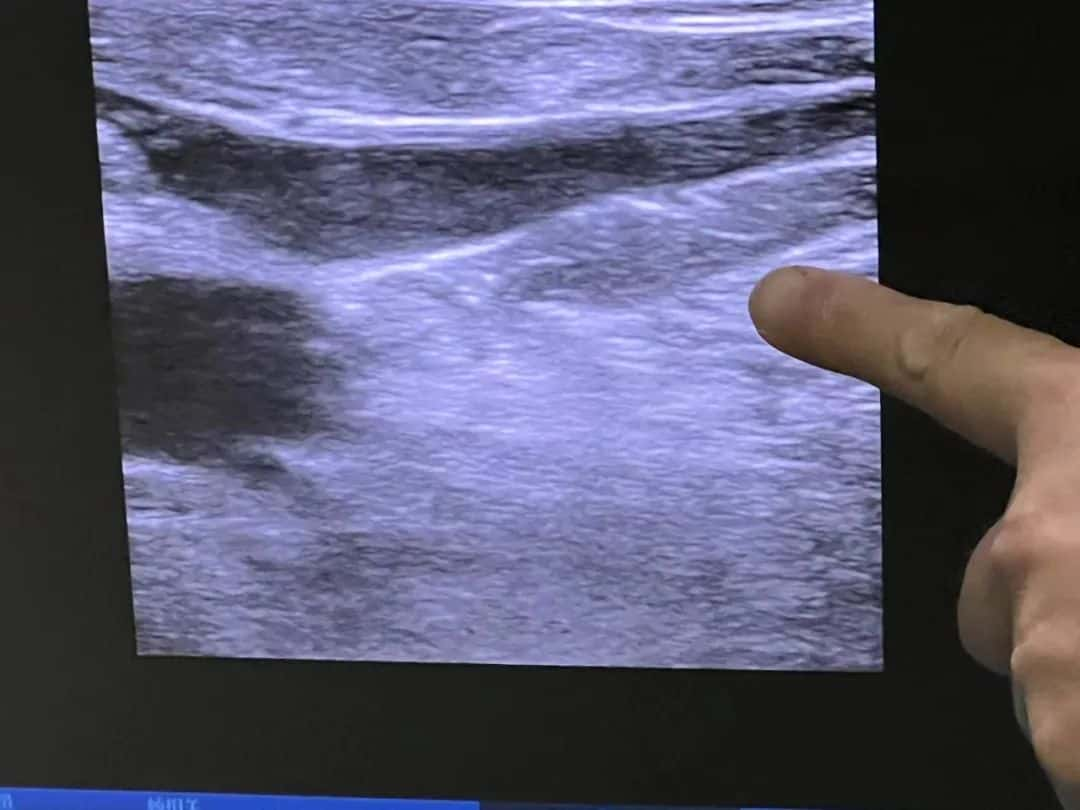

▲术前股隐交汇处超声图像